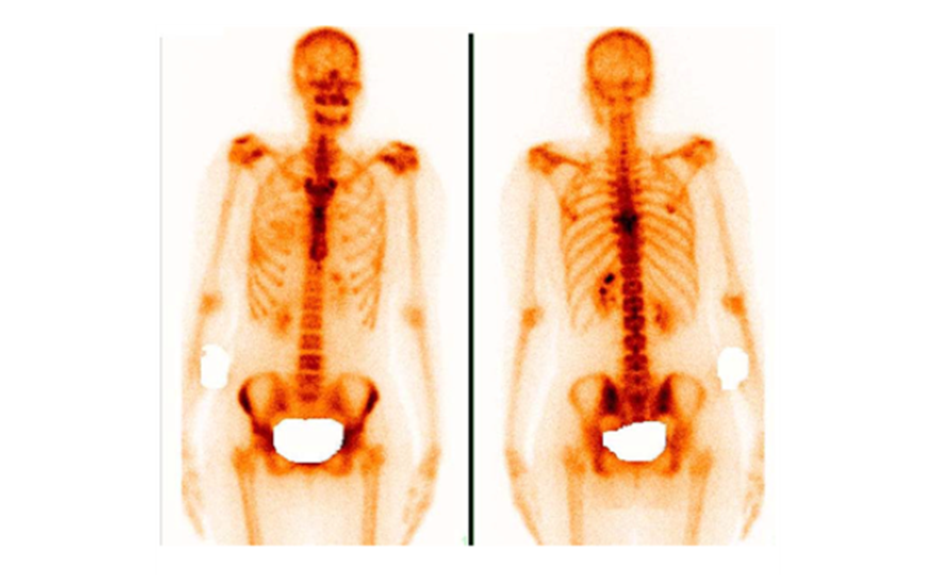

Остеосцинтиграфия позволяет оценить состояние всего скелета целиком за одну процедуру. В организм вводится безопасный радиофармпрепарат, который накапливается в местах с повышенным костным обменом, где может идти воспалительный, опухолевый или восстановительный процесс. Эти участки подсвечиваются на снимках, их называют «горячими очагами».

Горячие очаги на сцинтиграфии костей

Важно понимать, что метод очень чувствителен, но не всегда специфичен. «Горячий» очаг может быть и старым переломом, и артритом, и метастазом. Поэтому при обнаружении горячих очагов на сцинтиграмме в некоторых случаях необходимо пройти уточняющую диагностику (например, КТ или МРТ конкретного участка) для уточнения природы изменений.